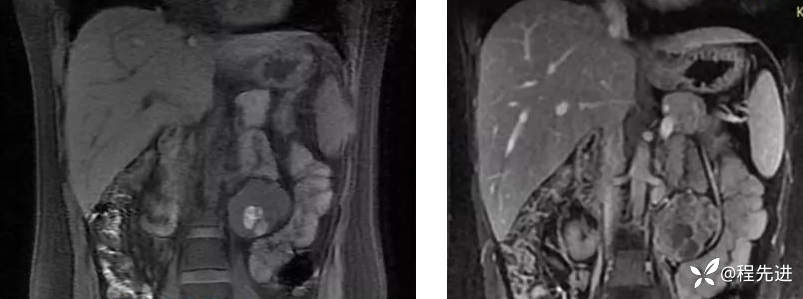

平扫,髓质期(冠状位)